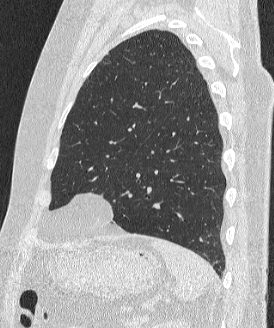

Во время исследования рентгеновская трубка томографа вращается вокруг исследуемой области и производит множество послойных снимков с шагом 0,5-1 мм. Полученные снимки поперечного сечения с помощью компьютерной программы могут быть преобразованы в 3D-изображения исследуемого органа или участка ткани. Это позволяет выявлять практически все заболевания легких на ранних стадиях и назначать своевременное лечение.

В медицинском центре «Доступная медицина» используется современный 128-срезовый компьютерный томограф TOSHIBA AQUILION CXL, на котором проводится сканирование легочной ткани. За счет увеличенного количества детекторов аппарат производит снимки с большой скоростью и минимальной дозой облучения. При этом инновационные цифровые приложения позволяют получить объемные изображения легочной ткани высокой четкости, контрастности и в мельчайших подробностях.